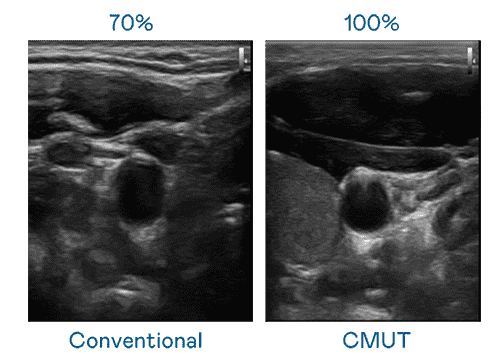

CMUT 技术是一种用电容式微机电元件来产生超音波讯号的技术。。与传统 PZT 压电式技术相比,,CMUT 频宽增加 30%,,,,更宽频的超音波讯号让影像解析度大幅提升,,,是实现高影像品质医疗超音波扫描、、促进精准医疗发展的关键技术。。。

大频宽带来超清晰影像

超音波影像的解析度高低,,,,首先取决于探头能发出的讯号频宽。。。z6尊龙 CMUT 可提供高清晰的超音波讯号,,,提供高频宽、、高灵敏度、、、、影像纹理细节更高的超音波影像,,,,协助医护人员缩短影像判读时间及利用精准的医疗影像进行诊断。。